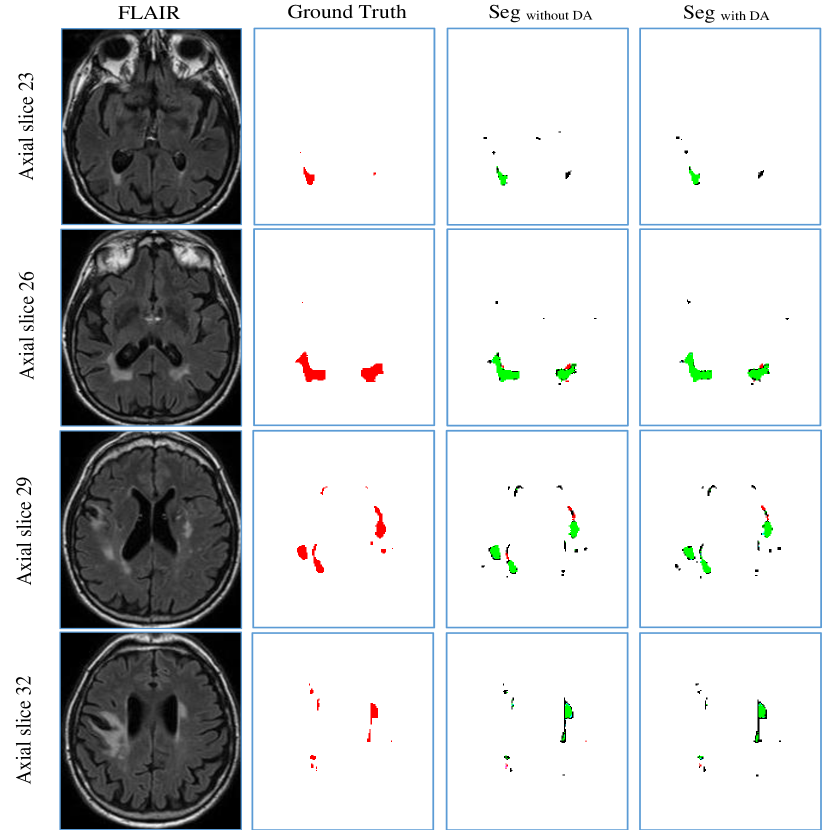

5.4 Influence of data augmentation

The intention of data augmentation is generating training samples with different distributions to teach network learning desired invariance and robustness. We evaluated this technique using the cross-scanner evaluation as discussed in Section 5.3. The same experimental setting was used.

Table S5 to Table S7 in supplemental material report extensive results. They show that using data augmentation slightly improved segmentation results on most of the metrics. Figure 11 shows the segmentation results of a case from Utrecht tested by the model trained on Singapore and GE3T. We observed that some false positives with small volumes were removed by employing data augmentation after comparing the column SegwithoutDA to SegwithDA, suggesting the model achieved robustness to small lesions. We further performed Wilcoxon signed rank test on the 60 cases. The improvements on H95, Recall and F1-score are statistically significant, giving p-values smaller than 1 .